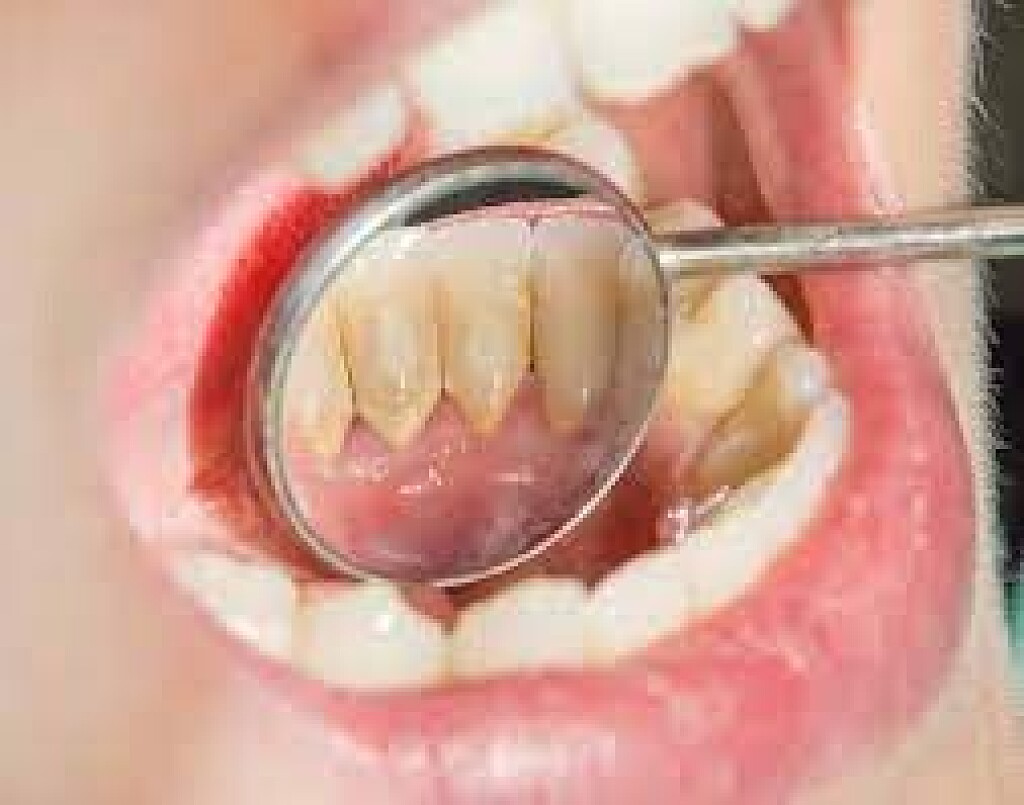

Gingivitis and Tooth Decay

Gingivitis is the initial stage of gum disease. Plaque buildup irritates gum tissue, making gums swollen and tender. Bleeding gums after brushing is a sign of gingivitis. Maintain proper oral hygiene and see your dentist if you notice these symptoms. As gum disease progresses, it can become more challenging to treat.

When plaque builds up in your mouth, it can turn into an even greater dental health threat: calculus. This formation, also known as tartar, is a calcified mass that adheres to your teeth. Calculus is classified as either supragingival or subgingival, depending on its location on your teeth. If left unremoved, subgingival calculus can lead to gum disease and tooth loss.

Tartar that accumulates on your teeth above the gumline and is easily seen by your dentist or dental hygienist is called supragingival calculus, according to the IJDHS article. But the tartar that forms below the gumline — and is therefore not immediately visible — is known as subgingival calculus. This type of calculus is usually dark brown to greenish black in color and can be detected with a dental instrument called an explorer.

It's important to note that, while you can clean plaque off your teeth with brushing and flossing, hard tartar can only be removed by a professional cleaning, explains the American Academy of Periodontology (AAP). Your dentist or dental hygienist uses special instruments that are designed to remove the calculus.

Calculus, including subgingival calculus, is associated with gingivitis, which is the first stage of gum disease, according to a review in the Journal of Health Sciences & Research (JOHSR). Typical early-stage gum disease symptoms include red, swollen gums and minor bleeding, according to the AAP. Luckily, the condition is often reversible with a good home care routine.

If left untreated, gingivitis can turn into periodontitis, where the plaque continues to spread beneath the gumline. When this happens, the AAP notes that the gum tissue eventually begins to pull away from the teeth, forming pockets that get infected. Pockets between the teeth and gums deeper than 4 millimeters may indicate that you have periodontitis, notes the Mayo Clinic.

When tartar builds up in the pocket, the bacteria can destroy the surrounding bone and tissue structures. Treatment of periodontitis usually involves scaling and root planing to remove all of the tartar, explains the Mayo Clinic. Periodontal surgery may also be necessary to treat any bone loss.

Preventing Calculus Formation

Since plaque is what forms tartar, preventing calculus involves cleaning plaque off your teeth regularly to prevent mineralization. This is why it's important to maintain a good oral care routine at home. Be sure to brush your teeth twice a day and floss daily. Using an antimicrobial mouthrinse can also help to reduce the amount of bacteria in your mouth. In addition, you should visit your dentist every six months for dental cleanings. At these cleanings, your dentist or dental hygienist will remove any tartar to prevent inflammation and gum disease.